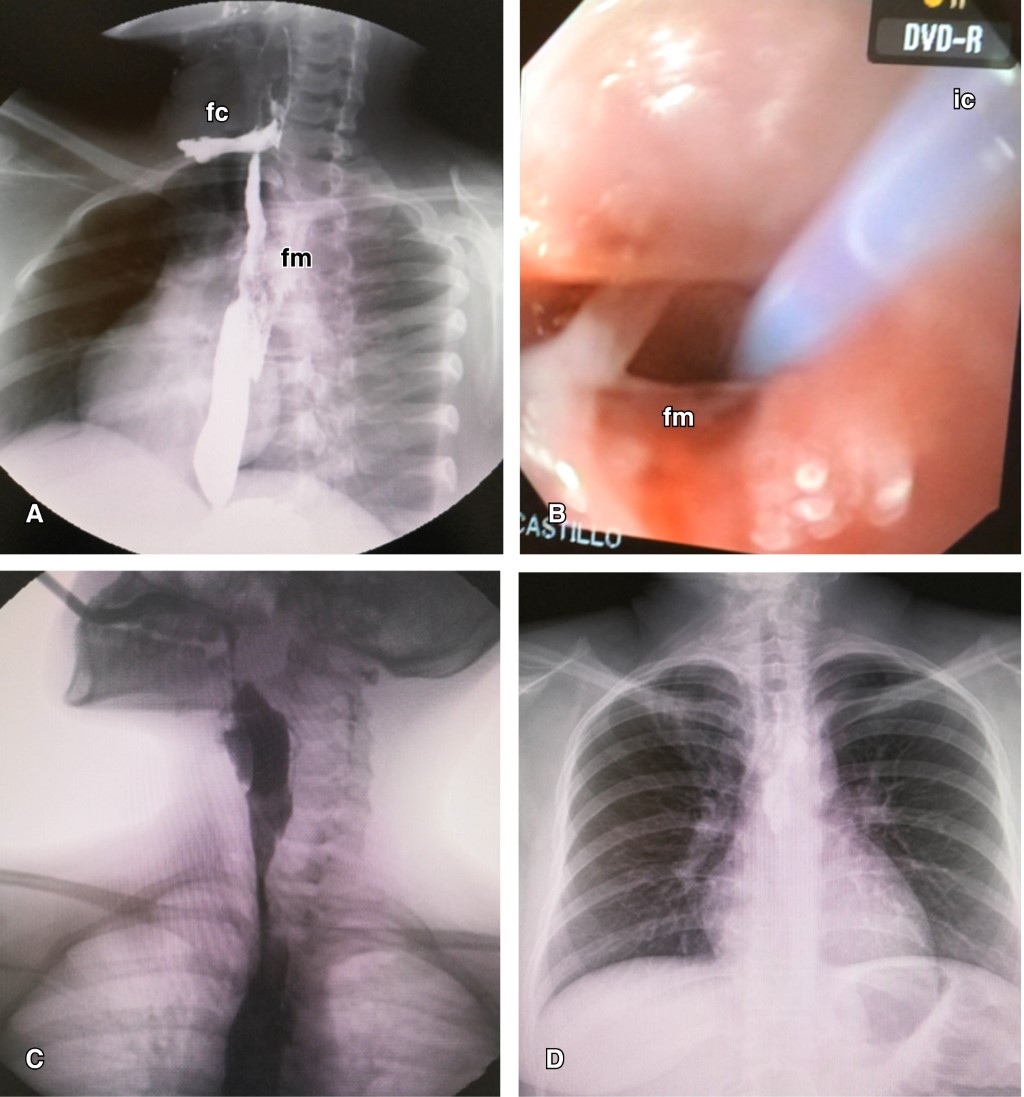

Paciente femenino de 16 años que inicia con vómitos y evacuaciones diarreicas secundario a gastroenteritis infecciosa, más tarde con aumento de volumen y dolor en región cervical izquierda, acudió al servicio de urgencias con disfagia, fiebre y enfisema subcutáneo cervical y torácico superior. En la radiografía cervicotorácica se identificaron enfisema subcutáneo, ensanchamiento mediastinal y neumomediastino. Una serie esofagogastroduodenal documenta fuga de material de contraste a nivel del esófago superior con extensión a mediastino con impresión diagnóstica de perforación esofágica cervical izquierda espontánea con compromiso mediastinal (Figura 1).

Se descartan antecedentes de ingestión o aspiración de cuerpo extraño, ingesta cáustica, y traumatismos, sin antecedentes de déficit neurológico ni trastornos de motilidad esofágica ni procesos otorrinolaringológicos inflamatorios o infecciosos previos. En la tomografía se corrobora perforación esofágica superior con disección enfisematosa cervical y torácica secundaria y presencia de un absceso mediastinal organizado con múltiples septos en su interior con volumen calculado de 600 mL de material purulento que excluye el lumen esofágico sin comprometer la vía aérea (Figura 2).

Para precisar el sitio de la potencial perforación esofágica se realizó un estudio endoscópico digestivo superior que se documenta en región lateral izquierda e inmediatamente superior a esfínter cricofaríngeo en hipofaringe, sitio de perforación con emisión de exudado purulento por donde se avanza a través del canal de trabajo 20 cm de una sonda de aspiración tipo Fogarty de 3 French obteniéndose 50 mL de pus y residuos necróticos (Figura 3).